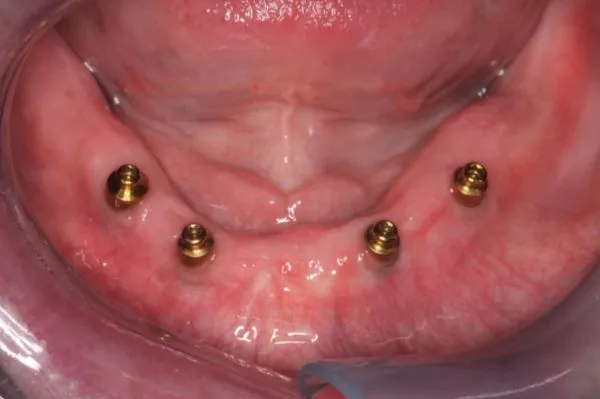

Implant Dentures

Dentures are a replacement for missing teeth that can be removed and put back into your mouth as you please. Depending on each individual patient case, they may receive full or partial dentures. Full dentures are used when all of the natural teeth are removed from the mouth and replaced with a full set of dentures. There are two types of full dentures.